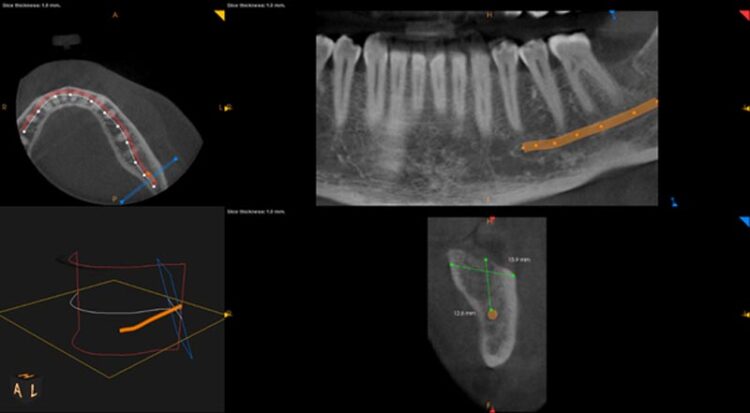

Following three months of healing, a CBCT scan was taken to assess bone dimensions and proximity of nearby anatomical landmarks, namely the inferior dental nerve and the lingual undercut of the mandible.

3-D radiographic examination showed sufficient bone available for the placement of a 5.8mm x 9mm BioHorizons Camlog tapered tissue level implant. Surgical placement of this implant involved a two-sided flap and there was no need for hard or soft tissue augmentation. The implant was placed with excellent primary stability and therefore a single-staged approach was followed with a healing abutment being placed at implant placement.